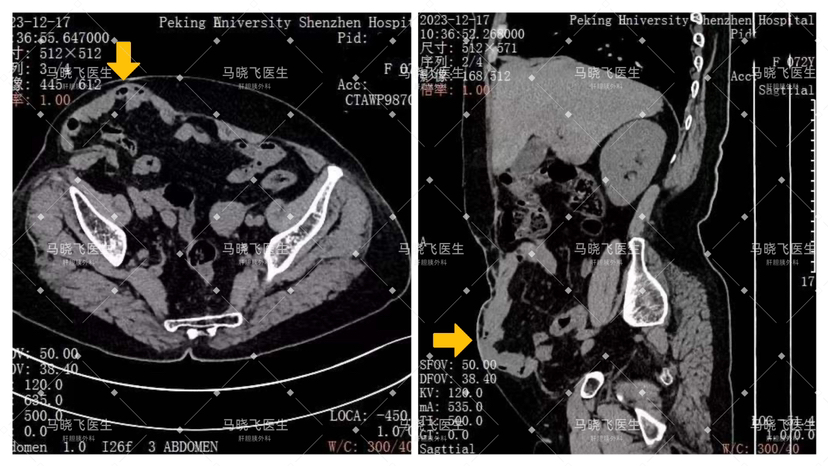

术前CT提示,患者腹壁的缺损已经达到了12cm×8cm,腹腔内部分肠管及其系膜向腹壁突出至皮下(图2)。